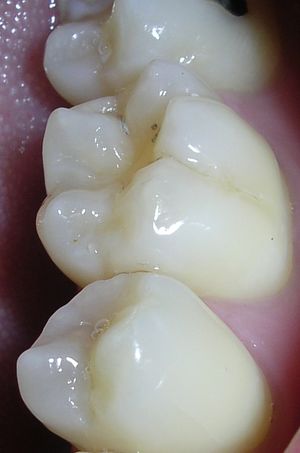

حدوث التسوس وتطوره

تقوم الحموض الناتجة من عملية تخمر السكاكر بحل العناصر المعدنية والعضوية التي تدخل في تركيب ميناء السن فتبدو المنطقة بيضاء طبشورية وذات ملمس خشن. ولدى تزايد إنتاج الحموض وعدم تطبيق الفلوريد الموضعي على الأسنان الذي يقوم عادة بإيقاف تطور التسوس، يتهدم الميناء وتصل الإصابة إلى العاج مشكلة حفرة التسوس التي يمكن ملاحظتها سريرياً ويبدأ الإحساس بالألم لدى التعرض إلى مؤثرات خارجية من سخونة وبرودة أو الضغط أثناء المضغ. عند إهمال معالجة التسوس في هذه المرحلة يزداد التخرب وتصل الإصابة إلى لب السن الذي يصاب بالالتهاب وترافقه موجات حادة من الألم وخاصة في أثناء الليل. إن عدم تطبيق المعالجة الملائمة في هذه المرحلة يؤدي إلى تموت اللب وإصابته بالتعفن وتتكون الخراجات الحادة والمزمنة والآفات الذروية التي تنتهي بقلع السن المصابة.